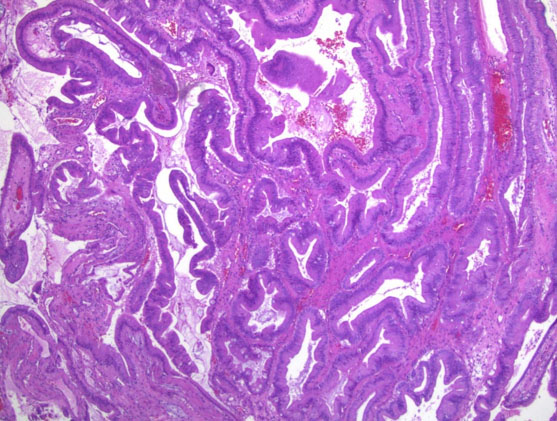

On physical exam, the patient had epigastric tenderness. Preoperative labs were notable for leukocytosis, hypoalbuminemia, direct hyperbilirubinemia (direct bilirubin of 2.8 mg/dL, total bilirubin of 2.9 mg/dL), elevated alkaline phosphatase, elevated aspartate aminotransferase, elevated alanine aminotransferase, and mildly elevated lipase. An abdominal ultrasound showed a thickened GB wall and a dilated common bile duct (CBD) (Figure 1). Due to suspicion of biliary tract disease, he underwent magnetic resonance cholangiopancreatography (MRCP), which showed a CBD diameter of 7.6 mm without evidence of choledocholithiasis or definitive evidence of cholecystitis (Figure 2). Because of concerns for a passed gallstone, he underwent inpatient laparoscopic cholecystectomy three days later.

Figure 1: Sagittal view of the gallbladder. The gallbladder is decompressed with a thickened wall to 4.0 mm. No evidence of cholelithiasis was seen.